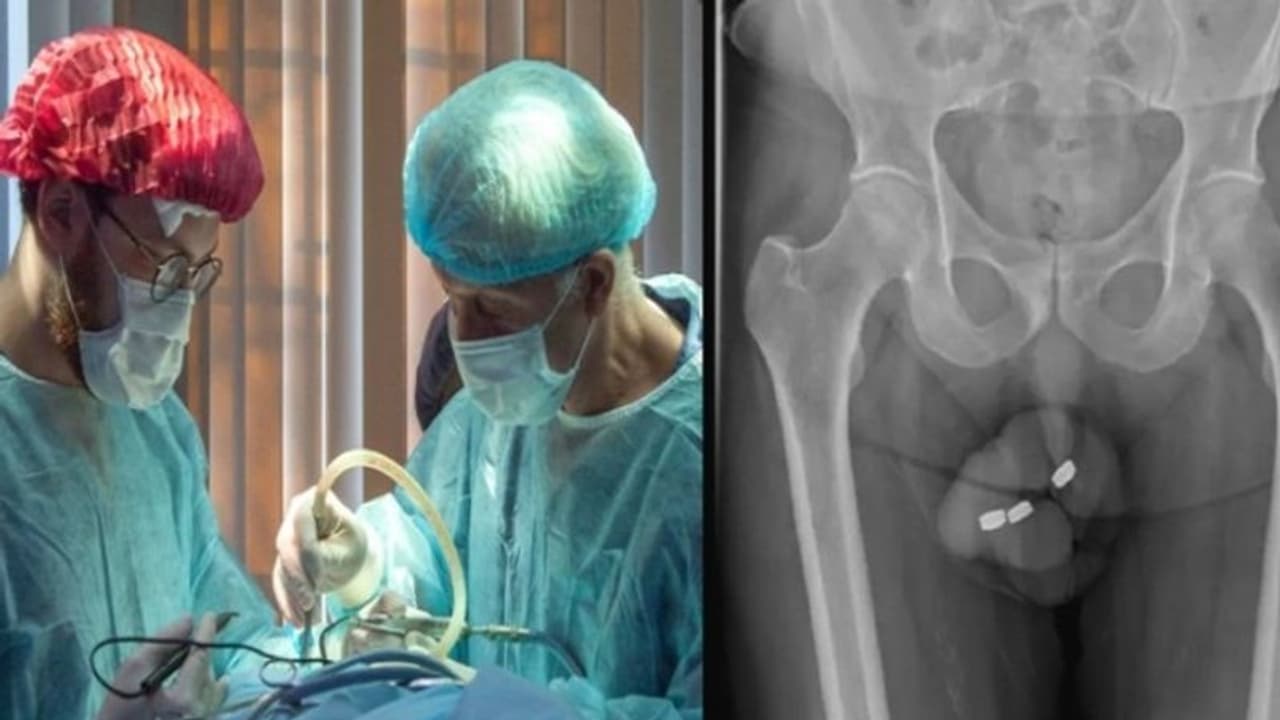

ನವದೆಹಲಿ (ಫೆ.18): ಹುಣಸೆ ಮುಪ್ಪಾದರೂ ಹುಳಿ ಮುಪ್ಪೇ ಎನ್ನುವ ಪ್ರಖ್ಯಾತ ಗಾದೆ ಕನ್ನಡದಲ್ಲಿದೆ. ಬಹುಶಃ ಈ ಮಾತನ್ನು ಇಲ್ಲಿನ ವೃದ್ಧನ ವಿಚಾರದಲ್ಲಿ ಖಂಡಿತವಾಗಿಯೂ ಹೇಳಬಹುದಾಗಿದೆ. ಲೈಂಗಿಕ ತೃಪ್ತಿ ಪಡೆದುಕೊಳ್ಳುವ ಸಲುವಾಗಿ ಶಿಶ್ನದಲ್ಲಿ ಮೂರು ಸಣ್ಣ ಪುಟ್ಟ ಬ್ಯಾಟರಿಗಳನ್ನು ಅಳವಡಿಸಿಕೊಂಡಿದ್ದ 71 ವರ್ಷದ ವೃದ್ಧನಿಗೆ ವೈದ್ಯರು ತುರ್ತಾಗಿ ಶಸ್ತ್ರಚಿಕಿತ್ಸೆ ಮಾಡಿದ್ದಾರೆ. ಆಸ್ಟ್ರೇಲಿಯಾದಲ್ಲಿ ಈ ಘಟನೆ ನಡೆದಿದೆ. ವಿಷಯ ತಿಳಿದ ಬೆನ್ನಲ್ಲಿಯೇ ವೈದ್ಯರು 24 ಗಂಟೆಯ ಒಳಗಾಗಿ ಶಸ್ತ್ರಚಿಕಿತ್ಸೆ ನಡೆಯಬೇಕು ಎಂದು ತಿಳಿಸಿದ್ದರು. ಶಸ್ತ್ರಚಿಕಿತ್ಸೆಗೂ ಮುನ್ನ ಬ್ಯಾಟರಿಯನ್ನು ತೆಗೆಯುವ ನಿಟ್ಟಿನಲ್ಲಿ ಸಾಕಷ್ಟು ಪ್ರಯತ್ನ ಮಾಡಲಾಯಿತಾದರೂ, ಎಲ್ಲವೂ ವಿಫಲಗೊಂಡಿತ್ತು. ಈ ವಿಲಕ್ಷಣ ಪ್ರಕರಣವು ಮಾರ್ಚ್ನ 'ಯೂರಾಲಜಿ ಕೇಸ್ ರಿಪೋರ್ಟ್ಸ್' ನಲ್ಲಿ ಅಧ್ಯಯನವಾಗಿ ಕಾಣಿಸಿಕೊಂಡಿದೆ. ಮೂತ್ರಶಾಸ್ತ್ರ ಜರ್ನಲ್ ಬಿಡುಗಡೆ ಮಾಡಿದ ಸಾಕಷ್ಟು ಘಟನೆಗಳ ವಿವರಣೆಯಲ್ಲಿ ಈ ಕೇಸ್ ದಾಖಲಾಗಿದೆ.

ಜರ್ನಲ್ನಲ್ಲಿನ ವರದಿಯ ಪ್ರಕಾರ, 13.5 ಮಿಮೀ ಅಗಲ ಮತ್ತು 3.2 ಮಿಮೀ ಎತ್ತರದ ಬ್ಯಾಟರಿಗಳನ್ನು ತೆಗೆಯುವ ನಿಟ್ಟಿನಲ್ಲಿ ವ್ಯಕ್ತಿಗೆ ದೊಡ್ಡ ಪ್ರಮಾಣದಲ್ಲಿ ವೈದ್ಯಕೀಯ ಆರೈಕೆ ಬೇಕಾಗಿತ್ತು ಎಂದು ತಿಳಿಸಲಾಗಿದೆ. ಈ ಹಿಂದೆಯೂ ಆತ ಲೈಂಗಿಕ ತೃಪ್ತಿ ಪಡೆಯುವ ನಿಟ್ಟಿನಲ್ಲಿ ತಮ್ಮ ಮೂತ್ರನಾಳಕ್ಕೆ ಬೇರೆ ರೀತಿಯ ವಸ್ತುಗಳನ್ನು ಸೇರಿಸಿಕೊಳ್ಳುತ್ತಿದ್ದ. ಯಾವ ಬಾರಿಯೂ ಈ ರೀತಿಯ ಸಮಸ್ಯೆ ಆಗಿರಲಿಲ್ಲ. ಆದರೆ ಈ ಬಾರಿ ಬ್ಯಾಟರಿಗಳು 'ಮೂತ್ರನಾಳದೊಳಗೆ ಹೆಚ್ಚು ಸಮೀಪದಲ್ಲಿ ಸೇರಿಕೊಂಡಿದ್ದವು. ಈ ಕಾರಣದಿಂದಾಗಿ ಅವುಗಳನ್ನು ತೆಗೆದುಹಾಕಲು ಅವರಿಗೆ ಸಾಧ್ಯವಾಗಲಿಲ್ಲ ಎಂದು ವೈದ್ಯರು ಹೇಳಿದ್ದಾರೆ.

ವ್ಯಕ್ತಿ ಆಸ್ಪತ್ರೆಗೆ ದಾಖಲಾದ ಬಳಿಕ, ವೈದ್ಯರು ತ್ವರಿತವಾಗಿ ಬ್ಯಾಟರಿಗಳನ್ನು ತೆಗೆದುಹಾಕಲು ಮುಂದಾಗಿದ್ದರು. ಹಾಗೇನಾದರೂ ಎರಡು ಗಂಟೆಯ ಒಳಗಾಗಿ ಇದನ್ನು ತೆಗೆಯಲು ಸಾಧ್ಯವಾಗದೇ ಇದ್ದರೆ ನೆಕ್ರೋಸಿಸ್ ಅಂದರೆ, ದೇಹದ ಅಂಗಾಂಶಗಳ ಸಾವಿಗೆ ಕಾರಣವಾಗಬಹುದು ಎಂದು ವೈದ್ಯರು ಎಚ್ಚರಿಸಿದ್ದರು. ಬ್ಯಾಟರಿಗಳನ್ನು ತೆಗೆದುಹಾಕಲು ವೈದ್ಯರು ಫೋರ್ಸ್ಪ್ಸ್ (forceps ) ಬಳಸಬೇಕಾಯಿತು.

ಈ ವ್ಯಕ್ತಿ ಕಳೆದ ಮೂರು ವರ್ಷಗಳಿಂದ ವೃದ್ಧ ನಿಮಿರುವಿಕೆಯ ಸಮಸ್ಯೆಯಿಂದ ಹೋರಾಟ ಮಾಡುತ್ತಿದ್ದ. ಅದಲ್ಲದೆ, ಆತ ಶಾಕ್ ವೇವ್ ಥೆರಪಿಗೆ ಕೂಡ ಒಳಗಾಗಿದ್ದರು ಎಂದು ಜರ್ನಲ್ನಲ್ಲಿ ತಿಳಿಸಲಾಗಿದೆ. ಆಸ್ಪತ್ರೆಯಿಂದ ಡಿಸ್ಚಾರ್ಜ್ ಆದ ಹತ್ತು ದಿನಗಳ ನಂತರ, ಅವರು ಶಿಶ್ನ ಊತ ಮತ್ತು ಮೂತ್ರ ಮಾಡುವ ವೇಳೆ ಸಮಸ್ಯೆ ಆಗುತ್ತಿದೆ ಎನ್ನುವ ಕಾರಣದೊಂದಿಗೆ ಆಸ್ಪತ್ರೆಗೆ ವಾಪಸಾಗಿದ್ದರು. ಈ ಹಂತದಲ್ಲಿ ಅವರ ಶಿಶ್ನದ ಚರ್ಮದ ಛೇದನ ಮಾಡಲಾಗಿತ್ತು. ಆ ಬಳಿಕ ದೊಡ್ಡ ಪ್ರಮಾಣದ ದ್ರವವನ್ನು ಹೊರಹಾಕಲಾಗಿತ್ತು ಎಂದು ಅಧ್ಯಯನ ತಿಳಿಸಿದೆ.

ಆಗಿರುವ ಗಾಯದ ಗಂಭೀರತೆನ್ನು ಗಮನಿಸಿದರೆ, ಶಿಶ್ನ ಮೂತ್ರನಾಳದ ಪುನರ್ನಿರ್ಮಾಣಕ್ಕೆ 3-ಹಂತದ ಶಸ್ತ್ರಚಿಕಿತ್ಸೆ ಅಗತ್ಯವಿರುತ್ತದೆ ಎಂದು ವೈದ್ಯರು ತಿಳಿಸಿದ್ದಾರೆ ಎಂದು ಅಧ್ಯಯನದಲ್ಲಿ ಹೇಳಲಾಗಿದೆ. ಸದ್ಯದ ಮಟ್ಟಿಗೆ ಅವರು ಅಪಾಯದಿಂದ ಪಾರಾಗಿದ್ದಾರೆ ಎಂದು ತಿಳಿಸಲಾಗಿದೆ.